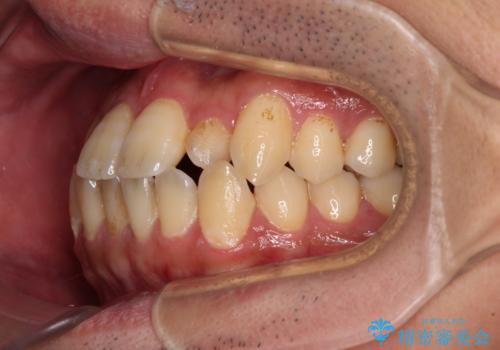

内側に引っ込んだ歯を治したい インビザラインの矯正治療

- 前歯のデコボコとクロスバイトを治したいとのことで来院された患者様です。

上下顎ともに歯列全体の側方拡大とIPR(歯と歯の間を削る)によってデコボコとクロスバイトが解消するように設計し、インビザラインにより治療を行うこととしました。

反対咬合特有の治療途中の前歯の干渉が長く続き、治療中に食事をとりにくく、ご迷惑をおかけしました。

前歯の咬み合わせの調整などを行い、安定した咬み合わせに仕上げることができました。